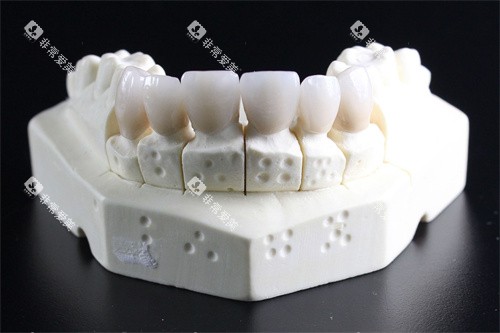

易美口腔一进门就像穿越到科幻片现场——全智能化设备、3D口腔扫描仪、隐形矫正模拟系统……妥妥的“黑科技代言人”。这里主打准矫正,尤其是隐形牙套(隐适美、时代天使)患者,医生会通过AI模拟提前预览矫正改善,连笑线弧度都能调整到“较好角度”。

明珠医院口腔科走的是“务实路线”,作为报销定点单位,补牙、拔牙、根管治疗等基础项目报销比例高,堪称北蔡牙科界的“性价比课代表”。更绝的是,它背靠综合性医院,遇到复杂病例(如牙周炎合并慢性病)能直接转诊内科,靠谱系数拉满。

疑难杂症终结者:种植牙失败修复、正畸正颌联合治疗等高难度项目,有医院医生坐镇。